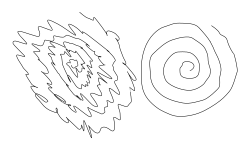

| Archimedean spiral drawings by a man with a unilateral essential tremor. The spiral on the left was drawn by the subject using the left hand, and the one on the right using the right hand. | |

Essential tremor (ET), also called benign tremor, familial tremor, and idiopathic tremor, is a medical condition characterized by involuntary rhythmic contractions and relaxations (oscillations or twitching movements) of certain muscle groups in one or more body parts of unknown cause.[6] It is typically symmetrical, and affects the arms, hands, or fingers; but sometimes involves the head, vocal cords, or other body parts.[4] Essential tremor is either an action (intention) tremor—it intensifies when one tries to use the affected muscles during voluntary movements such as eating and writing—or it is a postural tremor, which occurs when holding arms outstretched and against gravity. This means that it is distinct from a resting tremor, such as that caused by Parkinson's disease, which is not correlated with movement.[7] Unlike Parkinson's disease, essential tremor may worsen with action.

In mild cases, ET can manifest as the inability to stop the tongue or hands from shaking, the ability to sing only in vibrato, and difficulty doing small, precise tasks such as threading a needle. Even simple tasks such as cutting in a straight line or using a ruler can range from difficult to impossible, depending on the severity of the condition. In disabling cases, ET can interfere with a person's activities of daily living, including feeding, dressing, and taking care of personal hygiene. Essential tremor generally presents as a rhythmic tremor (4–12 Hz) that occurs only when the affected muscle is exerting effort. Any sort of physical or mental stress tends to make the tremor worse.[2]